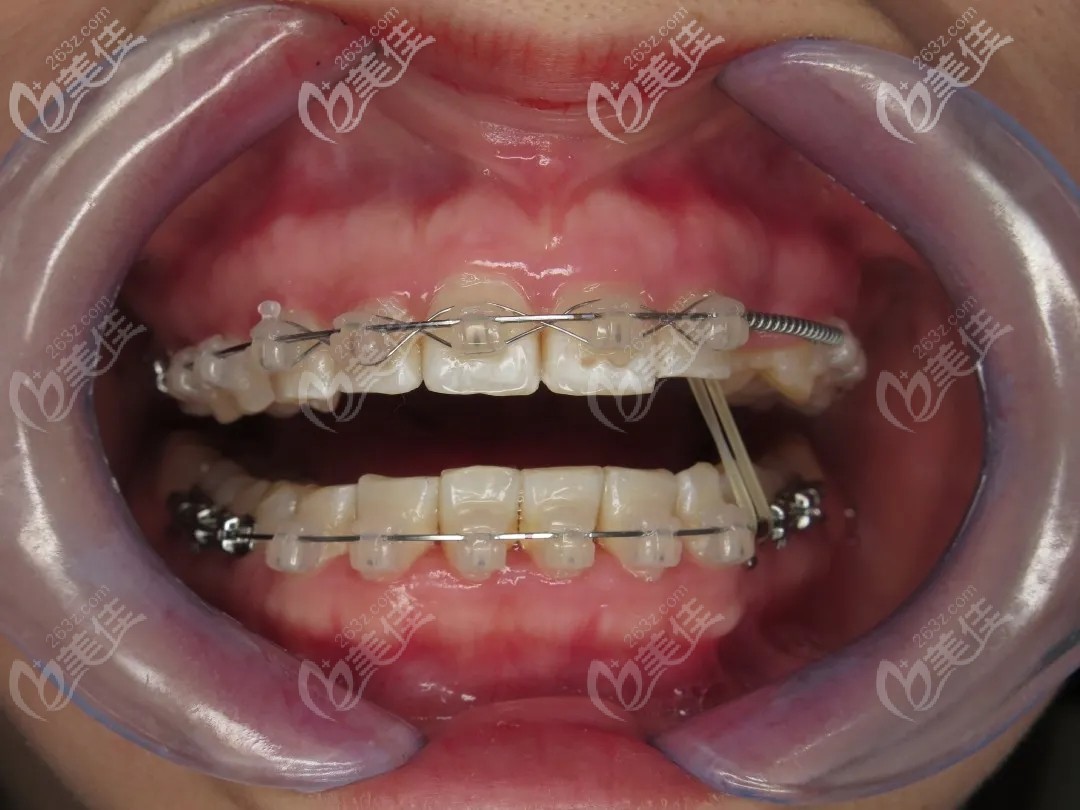

經(jīng)過內(nèi)心一通“打架”后,她選擇了陶瓷冰晶自鎖牙套,比全隱形牙套價(jià)格便宜,比傳統(tǒng)金屬牙套好看點(diǎn)。

終于在矯正滿1年的時(shí)候,藏匿的歪牙冒出了小頭,兩個(gè)月時(shí)間就長出了大半截,當(dāng)時(shí)簡(jiǎn)直高興的不得了。